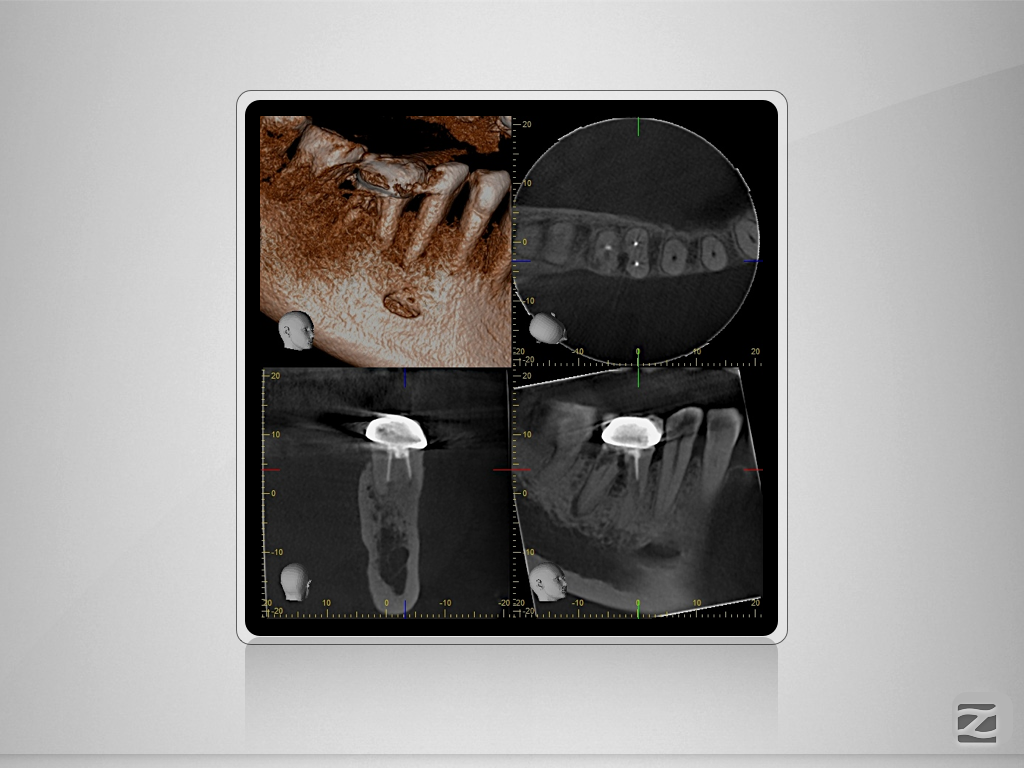

46D.007

2D vs. 3D (XXVIV)